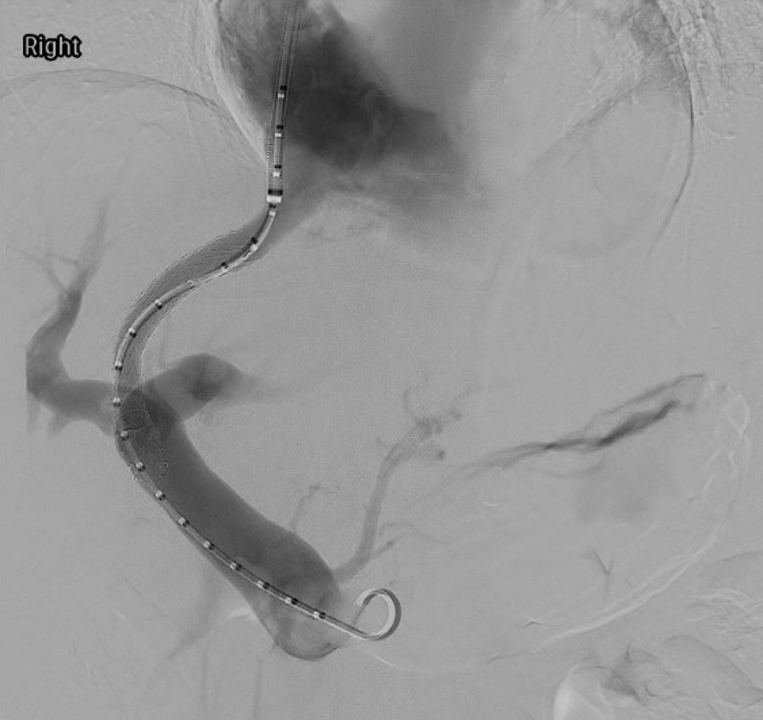

Stent placement is a suboptimal mechanical solution to chronic venous disease. We are doing translational research using a sheep model to study potential gene therapy strategies to minimize post-thrombotic venous changes and ameliorate the downstream quality-of-life complications.

- Reference: Li, N., Ferracane, J., Andeen, N., Lewis, S., Woltjer, R., Rugonyi, S., Jahangiri, Y., Uchida, B., Farsad, K., Kaufman, J.A. and Al-Hakim, R.A., 2022. Endovascular Venous Stenosis and Thrombosis Large Animal Model: Angiographic, Histological, and Biomechanical Characterizations. Journal of vascular and interventional radiology: JVIR, 33(3), pp.255-261. https://doi.org/10.1016/j.jvir.2021.10.036

Our research utilizes advanced flow imaging and computational fluid dynamics modeling to map complex blood flow patterns in healthy, diseased, and stented veins. We aim to uncover how chronic venous disease and interventions like stent placement alter hemodynamics, providing critical insights to optimize treatments for conditions like iliac vein compression (May-Thurner) syndrome and post-thrombotic sequelae.

- Reference: Li, N., Ferracane, J., Andeen, N., Lewis, S., Woltjer, R., Rugonyi, S., Jahangiri, Y., Uchida, B., Farsad, K., Kaufman, J.A. and Al-Hakim, R., 2022. Impact of Postthrombotic Vein Wall Biomechanics on Luminal Flow during Venous Angioplasty and Stent Placement: Computational Modeling Results. Journal of vascular and interventional radiology: JVIR, 33(3), pp.262-267. https://doi.org/10.1016/j.jvir.2021.12.006